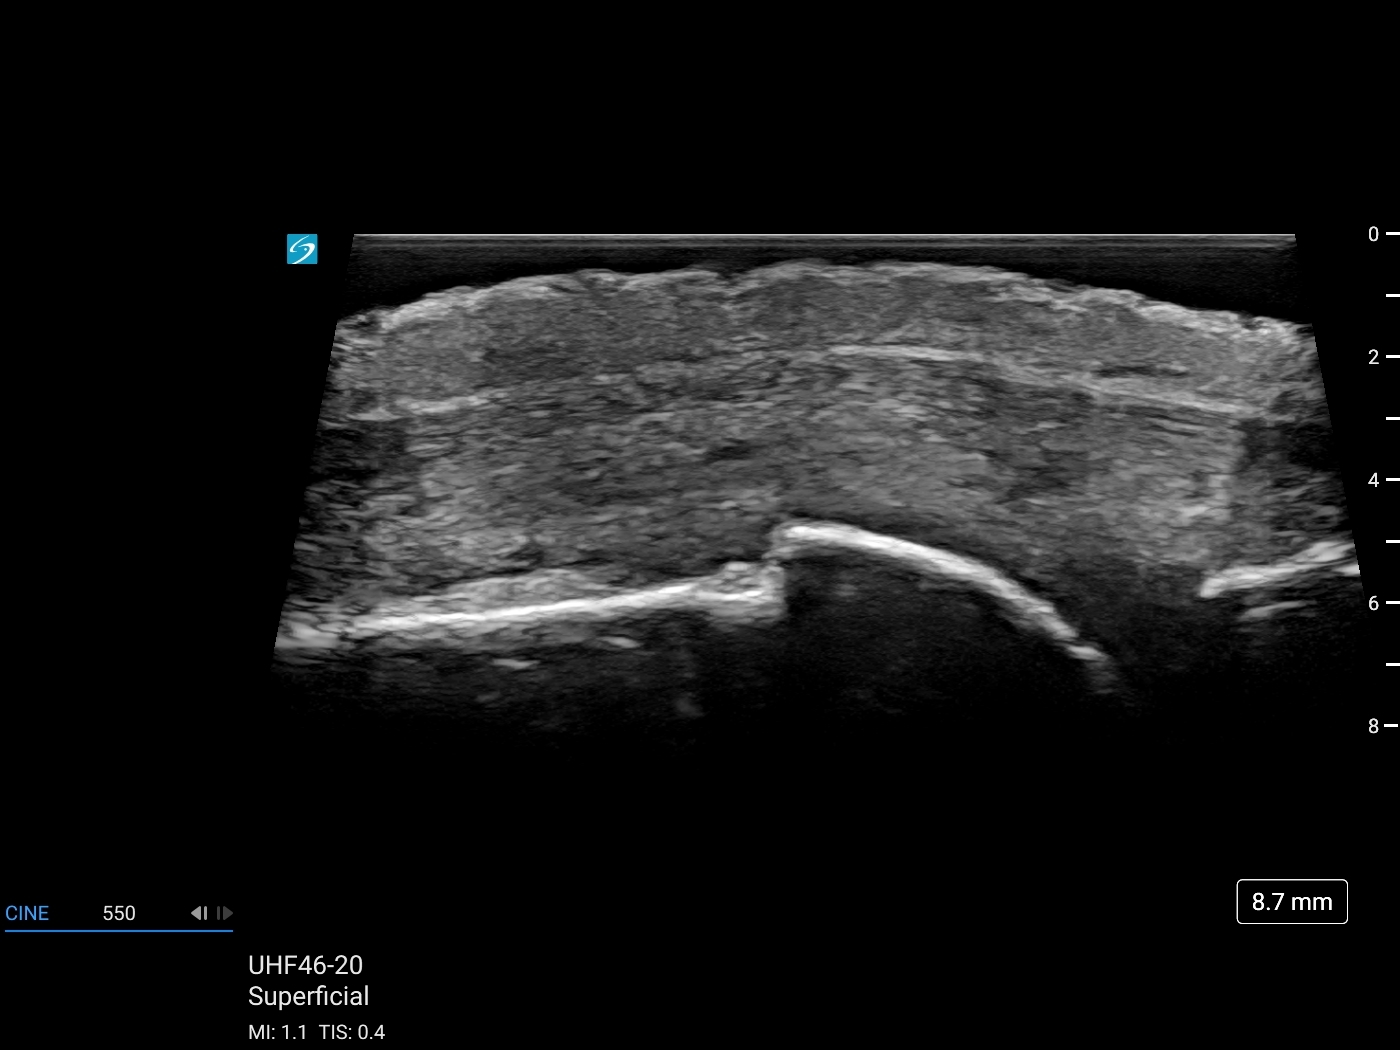

Evaluating soft tissue, connective tissue, and neurovascular structures of the dorsal hand is made possible with ultrasound and now elevated with Sonosite’s new ultra-high frequency transducer: UHF 46-20 MHz. Join Daniel Shelton for Part 1 of the Diagnostic Hand Ultrasound Series: ‘Introduction to the Dorsal Hand’ to review superficial anatomy of the dorsal hand, the benefits of ultra-high frequency for detailed precision, and learn techniques that help enhance image clarity and distinguish tissue layers.

MCP Joint Capsule without UHF

MCP Joint Capsule with UHF